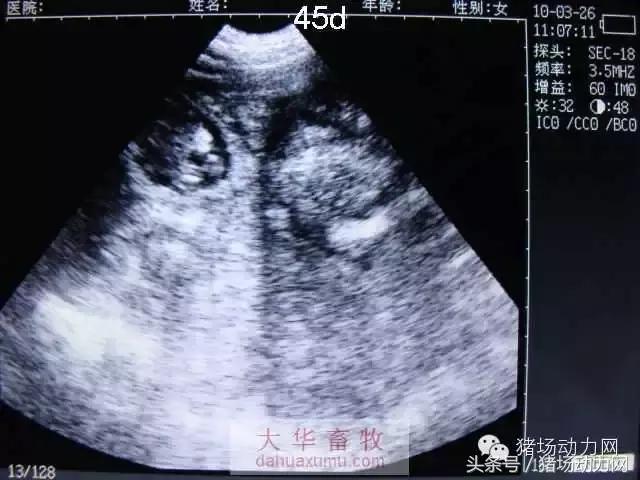

以下为怀孕母猪21天到90天之内的变化图:

45天